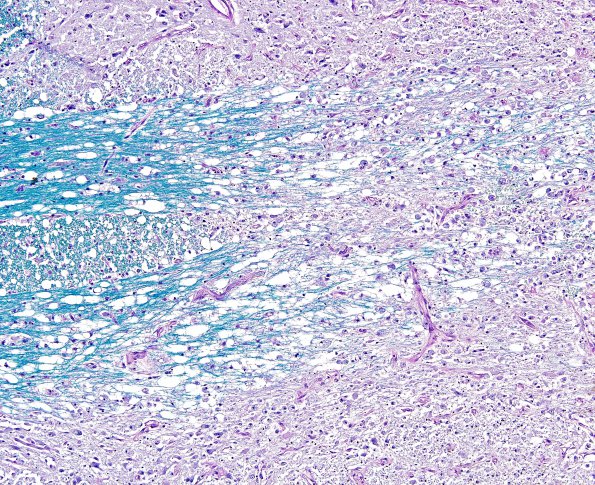

Washington University Experience | MYELIN (NON-IMMUNE MEDIATED) | Central Pontine Myelinolysis (CPM) | 8B3 CPM (Case 8) LFB-PAS 10X 2

8B3,4 Paired 10X images from this case comparing myelin (LFB-PAS) and axonal stained (Bielschowsky) material in near sequential images at multiple magnifications.